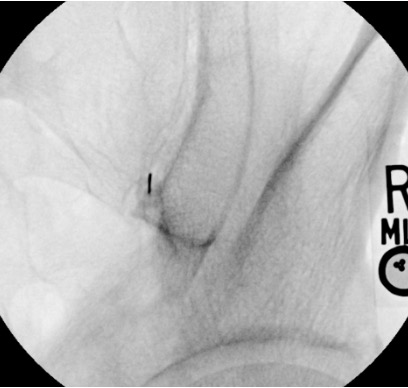

- Correct intra-articular: Contrast fills the inferior joint pouch; linear tracking along the posterior joint margin; gradual spread within the irregular joint contours

- Foraminal injection (too medial): Contrast flows into S1–S4 foramina — linear contrast extending medially from the sacral side; STOP, withdraw, redirect laterally

- Intra-osseous position: "Bone blush" — diffuse opacification of cancellous bone without joint space filling; STOP, withdraw, redirect

- Vascular uptake: Linear streaming contrast disappearing rapidly; STOP and reposition before injecting steroid

- Periarticular spread only: Diffuse pooling around joint without joint cavity filling; may still be therapeutic for ligamentous pain (periarticular injection)